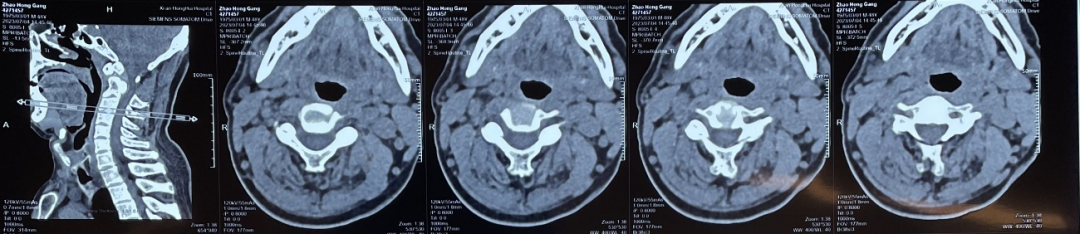

6.核磁图像、CT图像翻拍

以翻拍磁共振图像为例,翻拍时因为磁共振影像图很大,一张上多个图像,所以只拍一张照片,难以拍清楚细节,医生无法通过照片获取有效信息。

因此先拍一张整图,将一张磁共振图进行分区,并按分区顺序局部放大拍摄,尽可能的将片子上的细节拍摄清楚。CT图像翻拍操作一致。

(分区域拍摄1)

(分区域拍摄2)